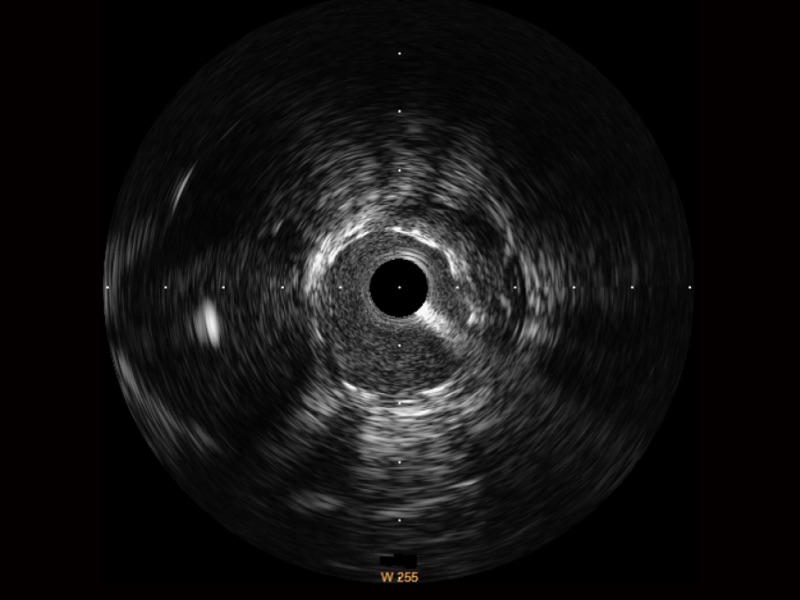

宽频成像,兼具高分辨力和更大穿透深度

太阳成tyc7111cc官网超宽频成像技术覆盖20-80MHz1或20-90MHz2频率范围, 提供优异的分辨力同时也保证充足的穿透深度

1.SonoSound? Crystal导管对比传统IVUS导管成像,太阳成tyc7111cc官网宽频IVUS图像的近场支架梁显影更细腻,远场中膜外血管仍清晰可辨,兼顾远中近,兼顾分辨力与穿透深度